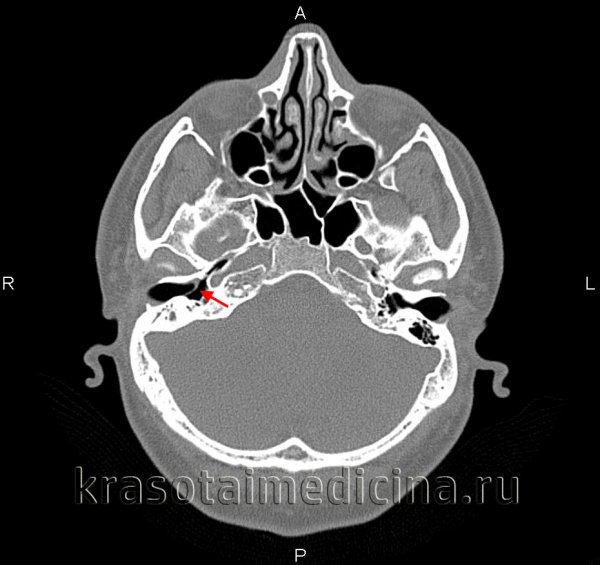

КТ височных костей. С обеих сторон диффузное снижение пневматизации ячеек сосцевидного отростка и пирамиды височной кости за счет отосклероза